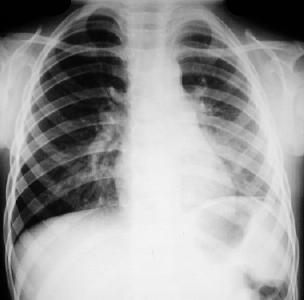

Rx. Tórax PA. (A). posterior a la insercion del tubo de tórax para drenaje pleural. radiopacidad difusa del hemitórax izquierdo, con colapso parcial pulmonar, desviación mediastinal hacia la derecha. Por proceso neumonico con derrame pleural.

Rx. Tórax PA.(B). Disminución de los espacios intercostales izquierdos, engrosamiento pleural severo , borramiento de los senos costo-frénicos, elevación hemi-diafragma izquierdo.escoliosis dorsal leve y poco aclaramiento del vertice por fibrosis pleural y atelectasia pulmonar.

Rx. Tórax PA.(C). Aumento compensatorio del volumen pulmonar derecho, mayor aclaramiento del vértice y disminución de espacios intercostales del hemitórax izquierdo. retracción del diafragma izquierdo, escoliosis marcada por fibrotorax severo.